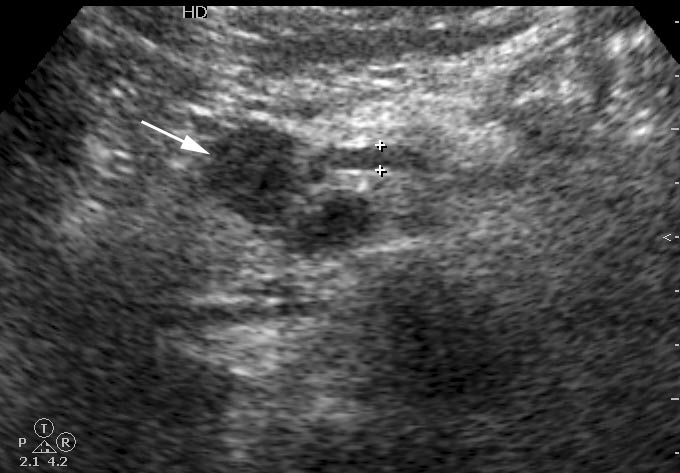

Женщина средних лет, боли в эпигастральной области. На УЗИ выявлено гипоэхогенное образование в области перешейка. Вирсунгов проток слегка расширен. При ЦДК в образовании определяется воспроизводимый кровоток.

Сонограмма панкреас, ее продольное сканирование.